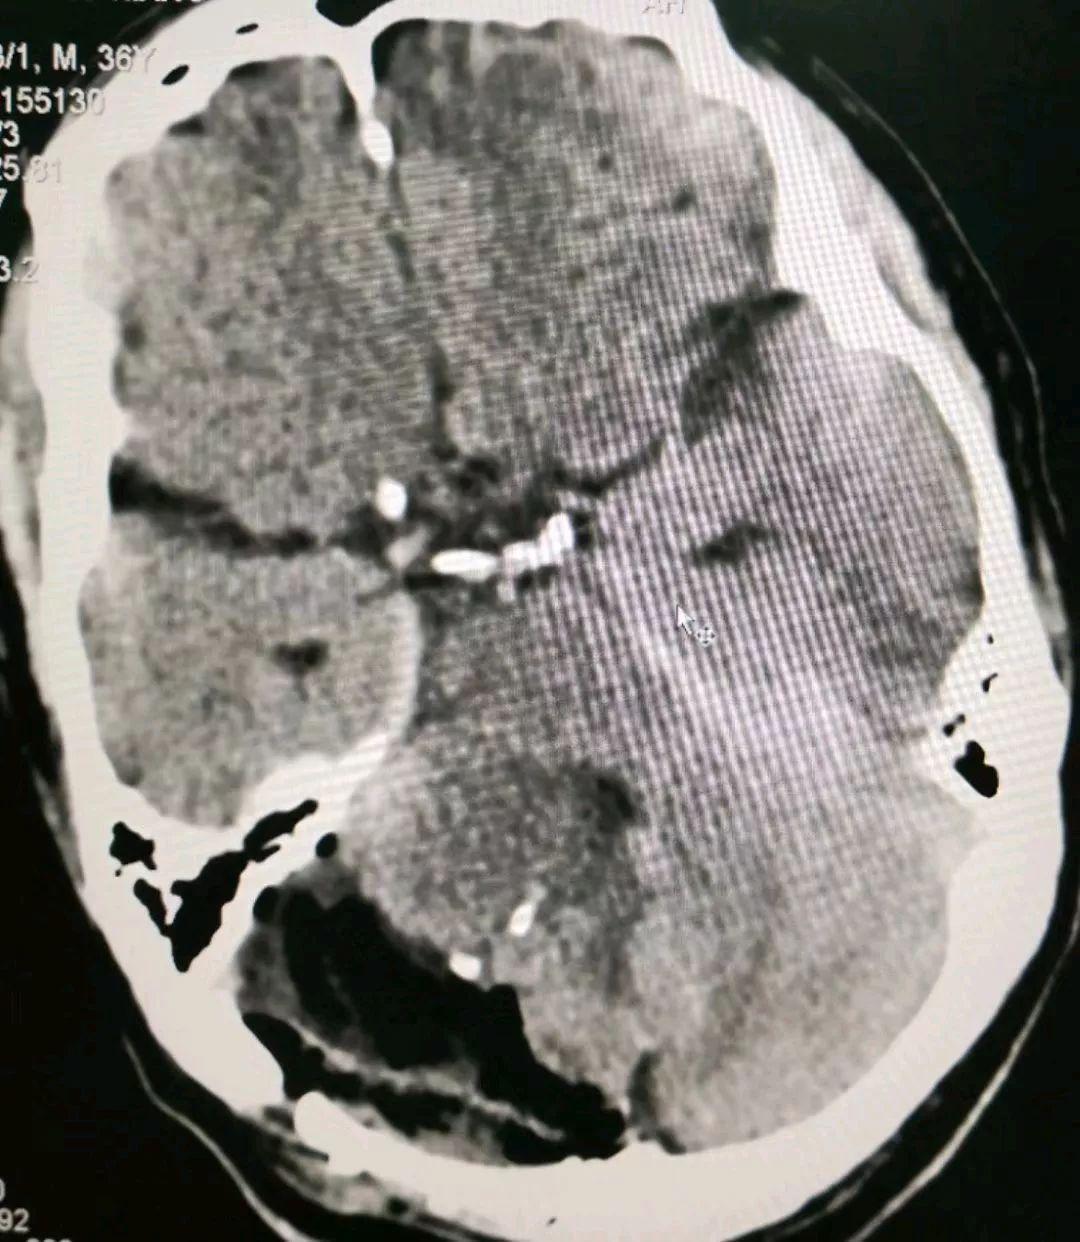

通过介入栓塞,向肿瘤内注入栓塞物质(下图),填充并堵塞血窦,阻止流入到肿瘤内,从而降低手术

复查造影提示肿瘤内大部分血窦被堵塞,肿瘤内血液供应明显减少,从而达到降低手术风险减少术后并发症的目的

栓塞后当天顺利切除肿瘤,术中出血只有300ml,手术非常顺利。患者今日术后第3天,无任何并发症。